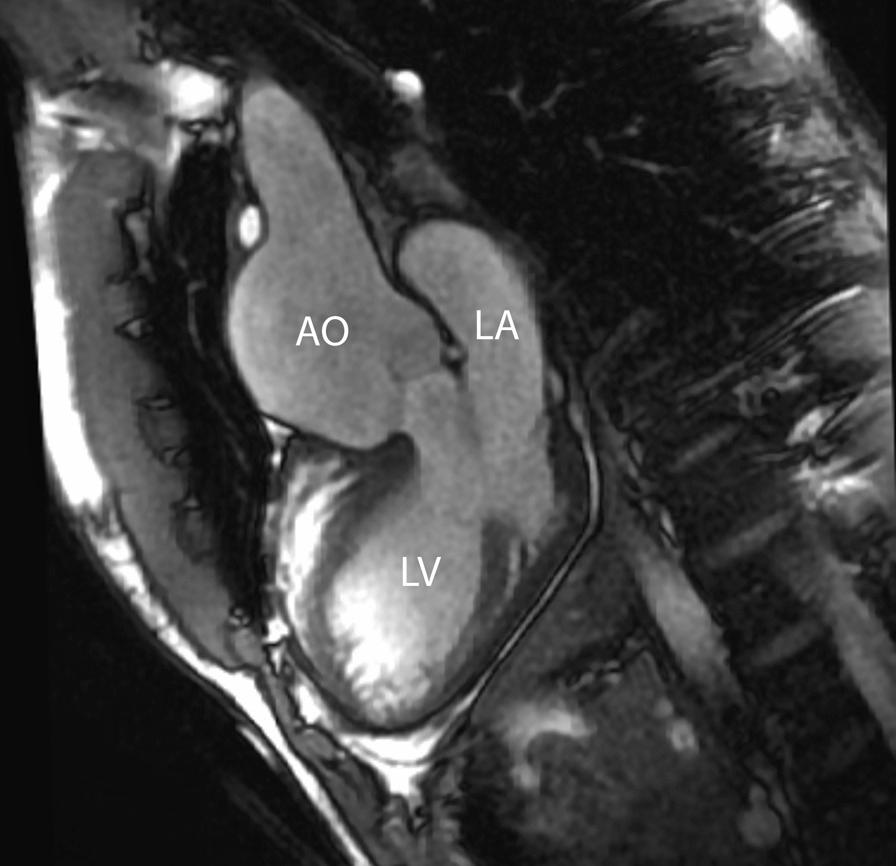

Cardiovascular magnetic resonance (CMR) has been utilized in the management and care of pediatric patients for nearly 40 years. It has evolved to become an invaluable tool in the assessment of the littlest of hearts for diagnosis, pre-interventional management and follow-up care. Although mentioned in a number of consensus and guidelines documents, an up-to-date, large, stand-alone guidance work for the use of CMR in pediatric congenital 36 and acquired 35 heart disease endorsed by numerous Societies involved in the care of these children is lacking. This guidelines document outlines the use of CMR in this patient population for a significant number of heart lesions in this age group and although admittedly, is not an exhaustive treatment, it does deal with an expansive list of many common clinical issues encountered in daily practice.

心血管磁共振(CMR)在儿科患者的管理和护理中已经应用了近 40 年。它已经发展成为评估最小的心脏的宝贵工具,用于诊断、介入前管理和随访。尽管在许多共识和指南文件中提到,但在儿科先天性心脏病和后天性心脏病领域,目前还缺乏一份由众多参与儿童护理的学会共同认可的、最新的、独立的、针对 CMR 使用的大型指南。本指南文件概述了 CMR 在该年龄段的许多心脏病变中的应用,尽管不能说是详尽的治疗方法,但它确实涉及了在日常实践中经常遇到的许多常见临床问题的广泛列表。